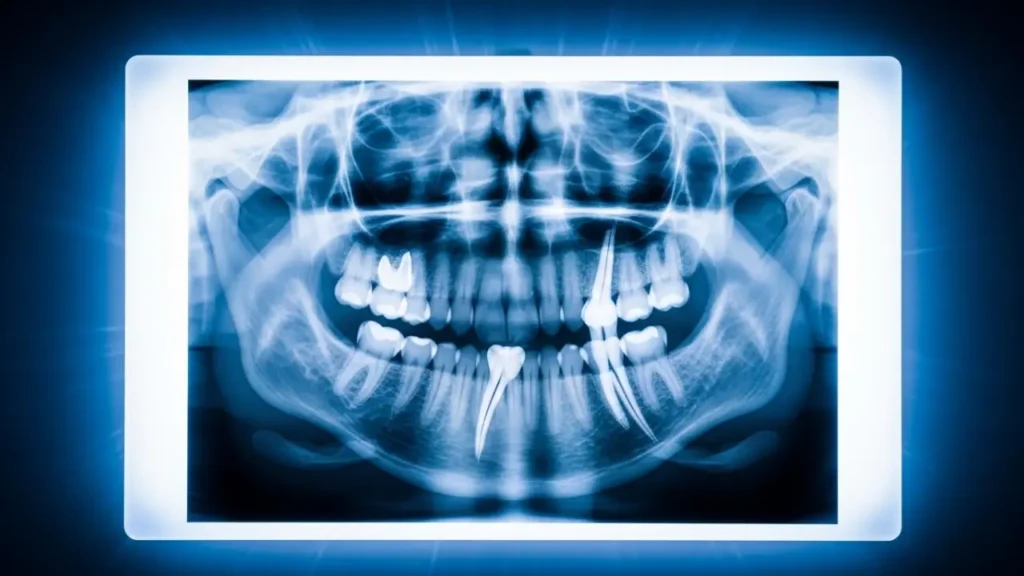

Not every wisdom tooth needs this procedure; that’s important to say upfront. The decision starts with imaging. A standard panoramic X-ray can give us early clues: roots that look darker near the nerve, roots that appear to narrow at the point where they cross the nerve canal, or roots that seem to ‘disappear’ into the nerve. These are the flags we look for.

When those warning signs show up, we follow up with a cone beam CT scan, essentially a 3D map of the jaw. That scan tells us exactly how close the roots are to the nerve, and in some cases, we can see the nerve canal running directly through the root itself. At that point, a coronectomy isn’t just an option; it’s the responsible recommendation.

3D cone beam CT scan of a wisdom tooth near the inferior alveolar nerve